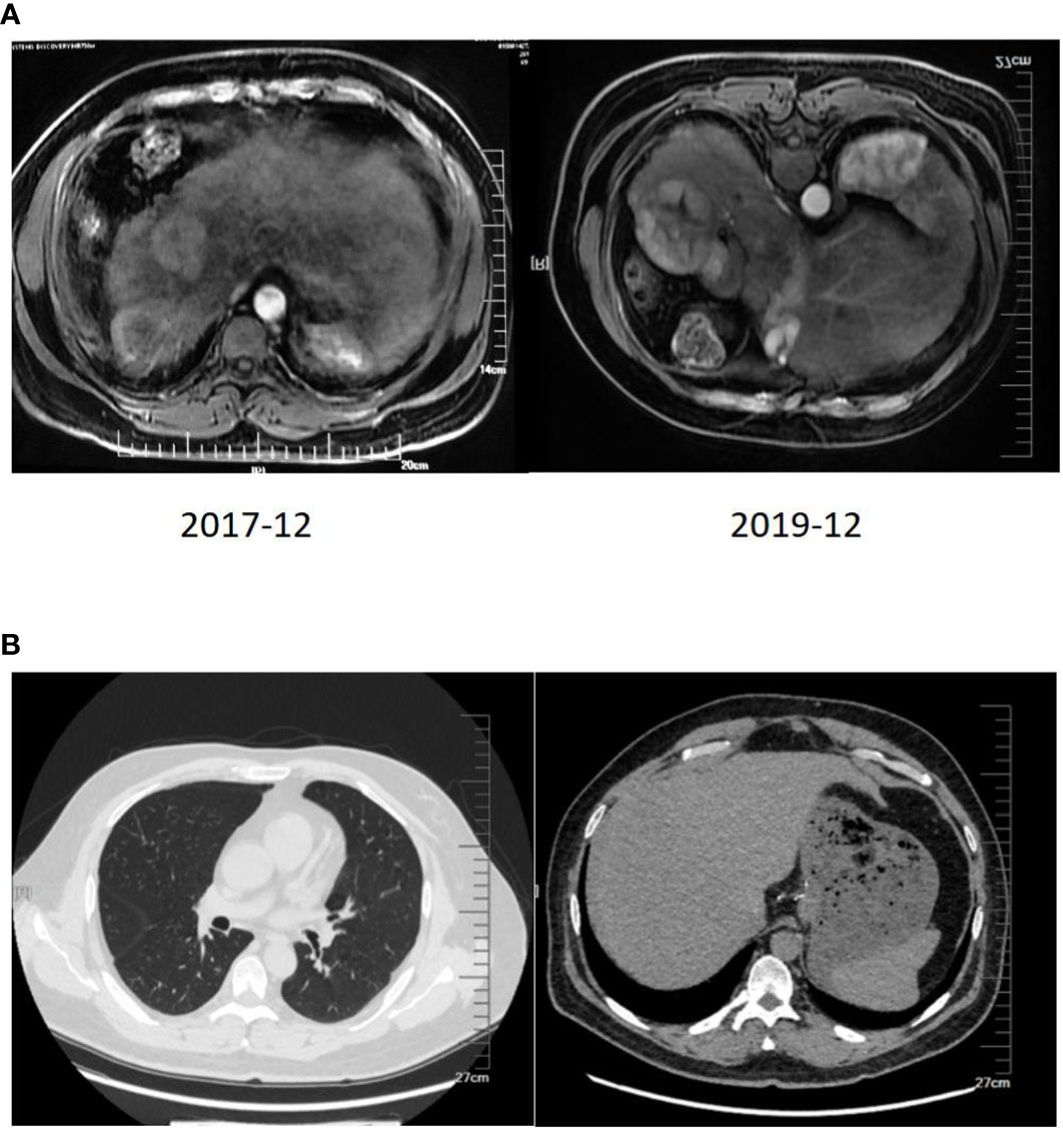

Chest and abdominal enhanced CT (CAECT) before the combination therapy showed irregular mass shadows in the superior segment of the right anterior lobe and multiple nodules in both lungs. Regular PET/CT in September 2018, after 8 months of treatment revealed shrinkage of lesions in the superior segment of the right posterior lobe, and the disappearance of most of the lung nodules. The CAECT on December 10, 2018, after 11 months of treatment showed that the foci on the right lobe were slightly enlarged, the metastases in both lungs disappeared, the primary foci on the liver were partially liquefied and necrotized, and no new foci were found. The CAECT after one year of treatment showed insignificant changes in the size of the hepatic lesions but increased necrosis and cystic degeneration.

The imaging examination (abdominal ECT) results of the patient are shown in Figure 2, and the foci size in the liver during the treatment and at different post-treatment time points by the abdominal ECT are shown in Table 1, while the changes between the prior-treatment and post-treatment MRI pictures of abdomen are shown in Figure 3A.

Figure 3

(A) Changes between the prior-treatment and post-treatment MRI pictures of the abdomen. (B) CT scan of the chest and abdomen one year after liver transplantation.

Chest ECT after one year of treatment showed no noticeable changes in the number and range of the lung nodules, and chest ECT after another 5 months with the same therapeutic scheme showed the disappearance of lung nodules. The final re-infusion of CAR T cells was completed in October 2019. The follow-up PET-CT on December 3, 2019, showed no significant changes except for the expansion of nodular necrosis in the superior segments of the right lobe and the metabolic activities in some regions.

The two-year combination therapy lowered the BCLC from stage C to stage B, reduced and maintained the AFP to a normal level, obtained a Child-Pugh class A of liver function, made most lung nodules disappear and the most hepatic foci necrotize and cystic degenerate, and obtained a PR. At this time of the treatment, whether the patient should continue to live with the tumor or undergo further conversion therapy should be decided. Based on the multidisciplinary team discussion, the patient was eligible for liver transplantation, and he underwent piggyback liver transplantation under general anesthesia on January 16, 2020, three months after the final re-infusion of CAR T cells. The surgical procedure went smoothly. The patient took immunosuppressive drugs, an anti-viral drug (Tenofovir), and anticoagulant drugs orally for a long period after surgery. Also, he continued with regorafenib at 80 mg for 3 months. The specimen of the total hepatectomy during the transplantation was submitted for examination. Pathological examination showed a giant type of moderately differentiated hepatocellular carcinoma with extensive necrosis and local cystic degeneration in the right posterior lobe, and a small type of moderately differentiated hepatocellular carcinoma with focal necrosis in the right anterior lobe. Cancer cells were arranged in a trabecular and cord-like manner according to the hematoxylin-eosin (HE) staining. Immunohistochemical staining showed GPC3(+), Hep-1(+), HSP-70(+), CK19 (–), Ki67(+20%), HBsAs (+), HBcAg (–), CD34(+), and Masson staining showed the formation of collagen fiber septa in the liver tissue, including pseudolobulations. The follow-up rechecks of the AFP level and the chest and abdominal CT (Figure 3B) were conducted after one year of the transplantation. The patient has now returned to normal work and life.